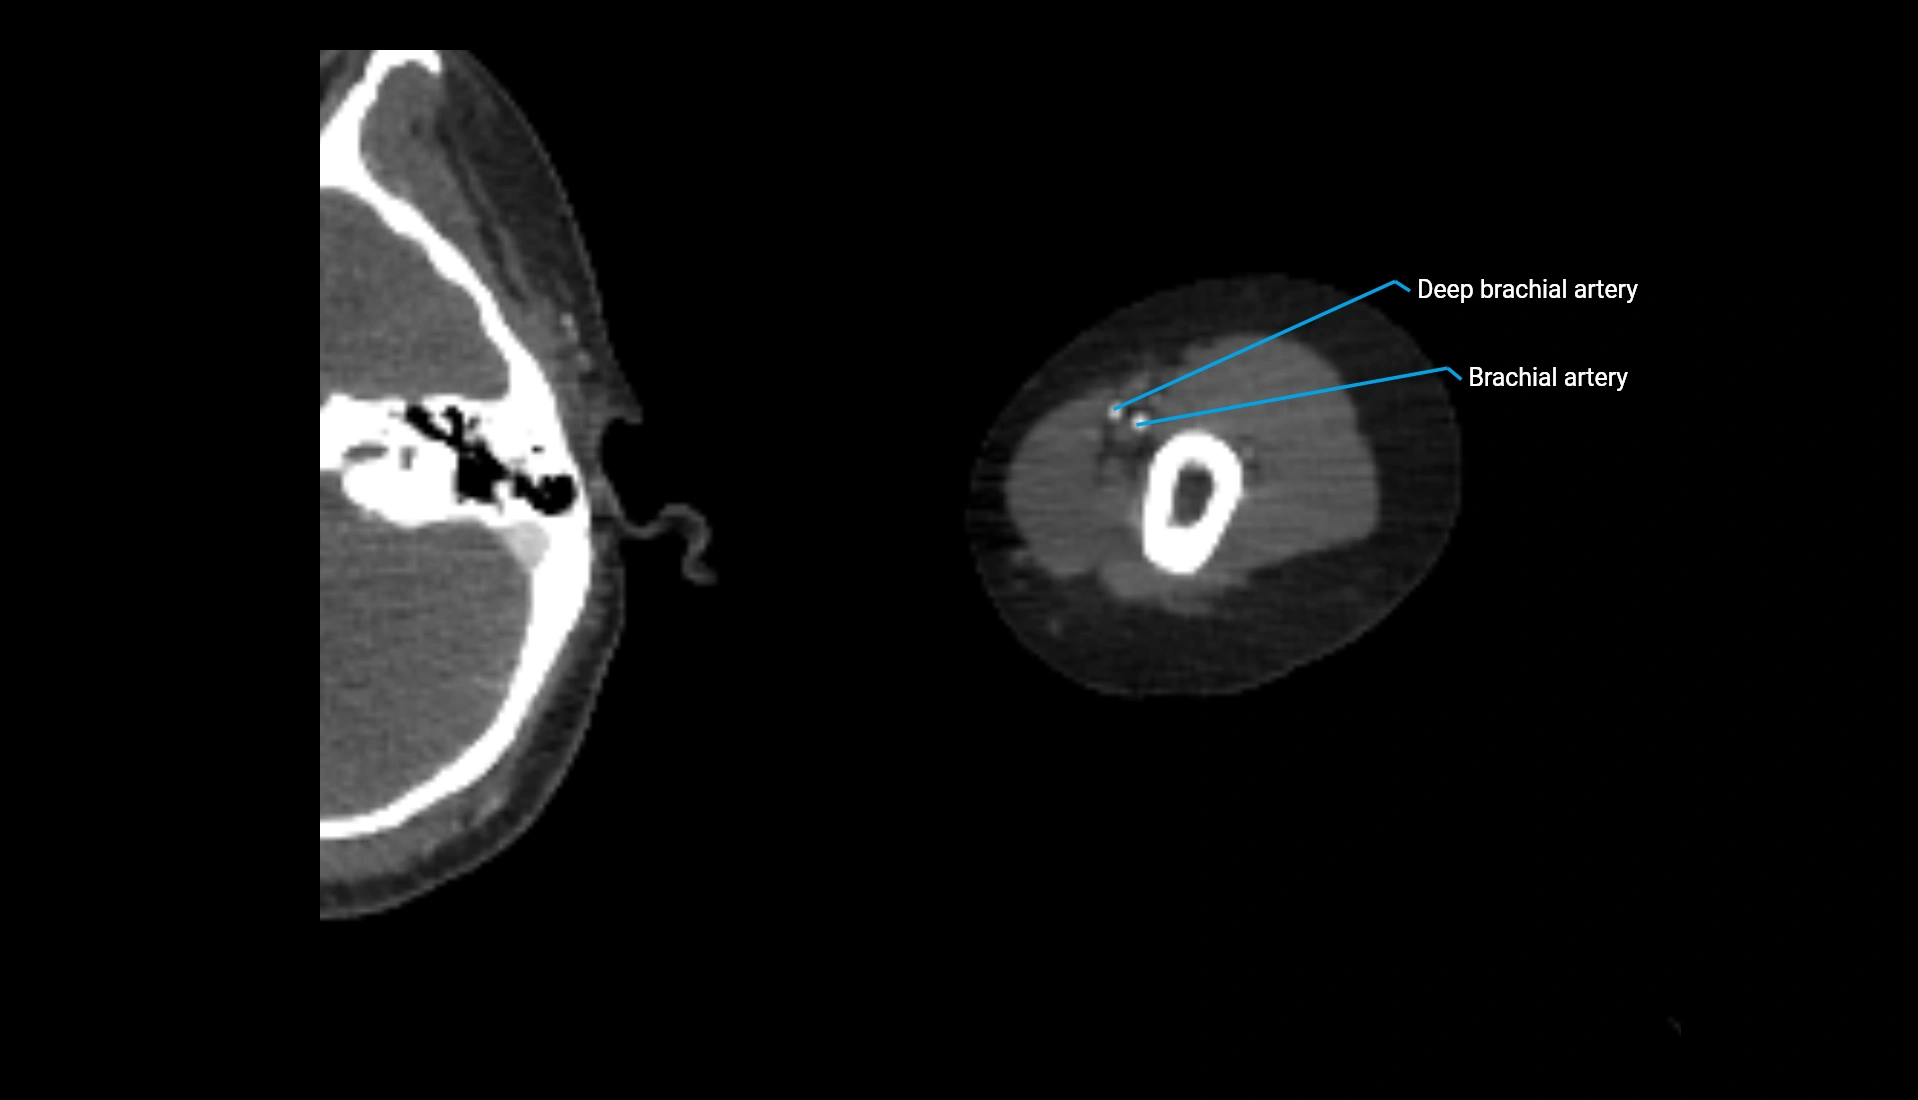

CT Appearance

Non-Contrast CT:

• Cortex: High-density, sharply defined

• Subchondral bone: Dense cancellous matrix

• Articular surface: Smooth concave contour articulating with the capitellum

• Excellent for evaluating bone integrity, alignment, and subtle fractures

Post-Contrast CT:

• Bone: No enhancement

• Joint capsule and synovium: Mild enhancement outlining the joint

• Improves contrast between soft tissues and bony margins

• Useful in detecting subtle joint abnormalities or postoperative changes